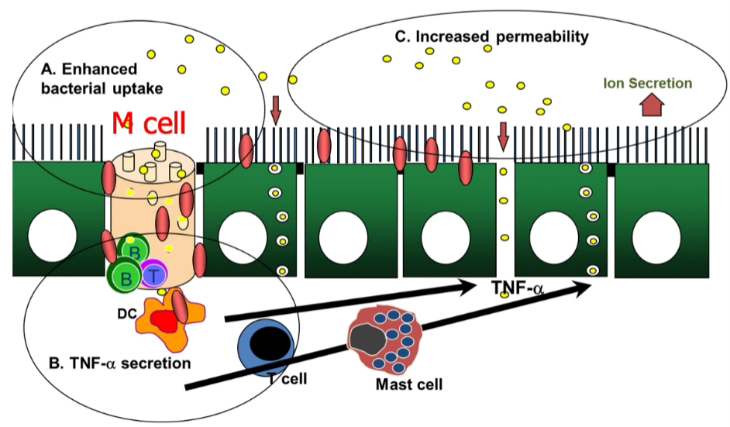

Hur sker signaleringen vid Crohns som kan leda till störd barriär?

- Peyerska plack täcks av follikelassocierat epitel som innehåller M-celler (inkörsport till underliggande vävnad)

- Vissa bakterier kan använda denna passage och då ger aktivering av inflammatoriska celler (T-cell ex) med ökad TNF-a-utsöndring som följd vilket ger ökad permeabilitet/inflammation

- Ofta ses just sår över peyerska plack i ileum i tidigt skede

Hur sker signalering vid ulcerös colit som kan leda till störd barriär?

- Förändrat mukuslager (tunt) kan ge ökad permeabilitet med ökat upptag av bakterier och antigen

- Dendritcell har tentakel ovanför epitelcellerna med TLR och samplar och aktiveras varför NF-kB-vägen aktiveras vilket ger transkription av proinflammatoriska cytokiner vilket gör dendritcellen än mer aktiverad så den aktiverar naiva T-celler till Th2 som utsöndrar IL-4, NKT utsöndrar IL-5 och IL-13. Dessa cytokiner har direkt effekt på tarmens barriär genom ökad genomsläpplighet vid tight junctions

- Blir ond cirkel med ökad permeabilitet och underliggande inflammation